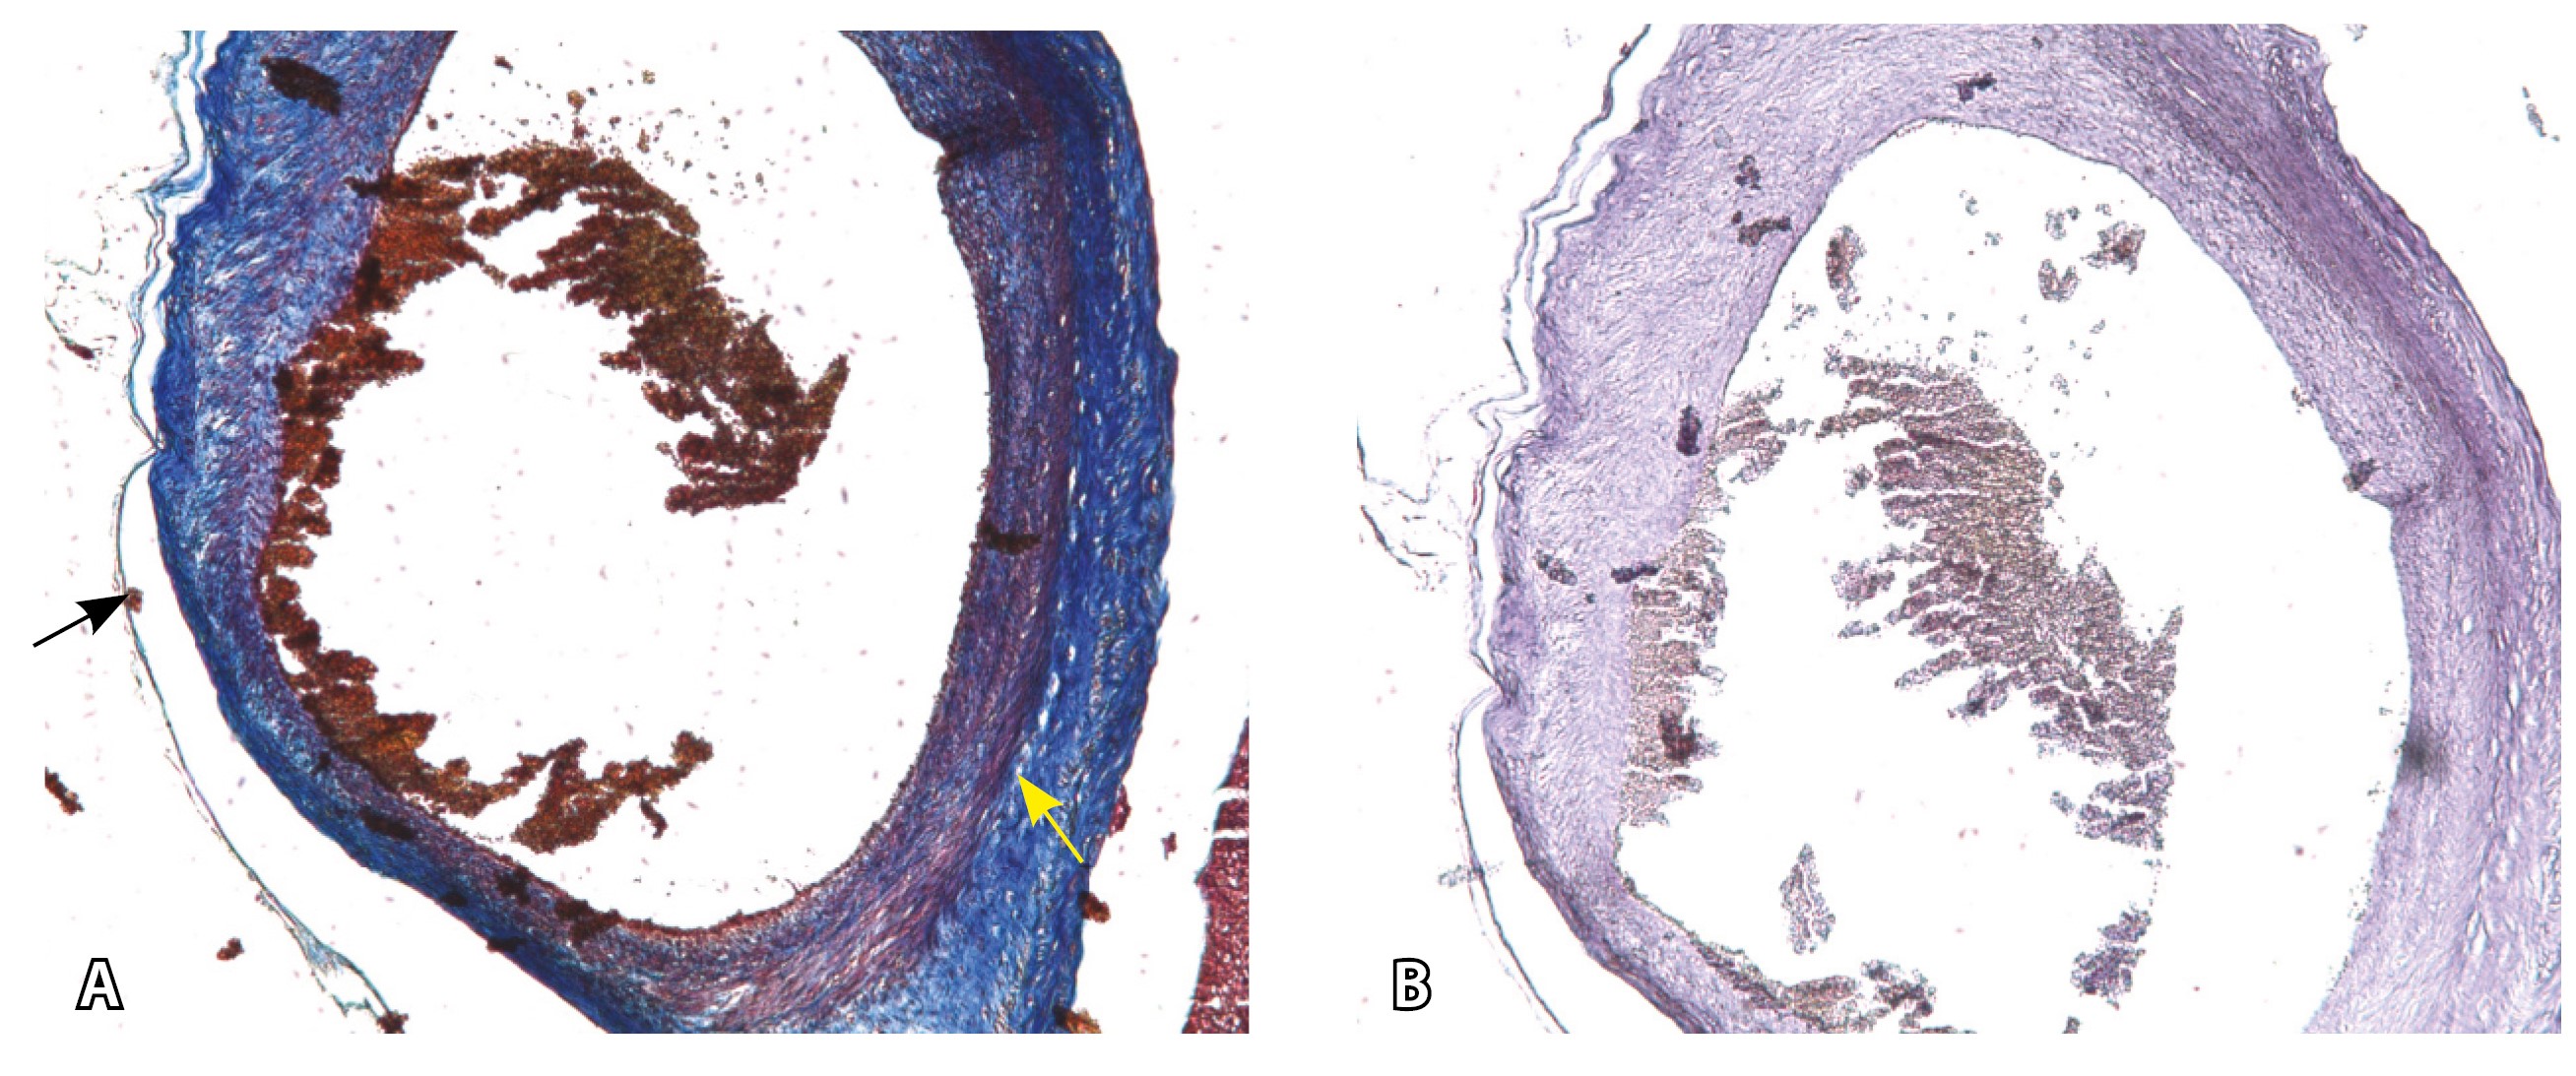

Рис. 13. Самые крупные сосуды в пределах серозной оболочки стенки матки: А, Б – серийные срезы артерии; × 50. При окраске по Маллори (А) видна тонкая полоска мезотелия (черная стрелка), слабо дифференцированная мышечная стенка артерии, вокруг нее – плотная коллагеновая оболочка (желтая стрелка), в просвете определяются тромботические массы. При окраске по Вейгерту (Б) наблюдается полная потеря внутренней и внешней эластических мембран

Эластический каркас представлен сетью тонких волокон, без концентрации на внутреннюю и внешнюю мембраны. Однако маркер СD34 констатирует сохранение эндотелия, что свидетельствует о том, что по артериям циркулирует кровь, не сворачиваясь (рис. 13).

На микропрепаратах васкуляризация серозной оболочки представлена множеством крупных сосудов, идущих в разных направлениях и анастомозирующих друг с другом. Возможно, имеются артериовенозные соустья. На серийных срезах также видно, что в стенках артерий трудно различимы два слоя миоцитов (продольный и поперечный). Со стороны адвентиции они окружены толстым «футляром» из грубоволокнистой голубой ткани (при окраске по Маллори). Она проникает в стенку артерий, замещая мышечный слой (рис. 12).

Рис. 12. Истончение миометрия; в составе серозной оболочки видна крупная артерия, окруженная плотной соединительной тканью. А – cосуды в составе серозной оболочки (окраска по Маллори; × 200), не дифференцированная на мышечные оболочки стенка артерии, справа – вена, оба сосуда покрыты фиброзной оболочкой, внизу виден слой мезотелия в составе серозной оболочки; Б – серийный срез тех же сосудов при окраске на выявление эластических волокон, сосуд с соединительнотканной муфтой (окраска по Вейгерту; × 50): определяется полная дезорганизация эластичного материала в стенке; стрелкой указан мезотелий (аналог pl. increta, PAS 2 по FIGO)